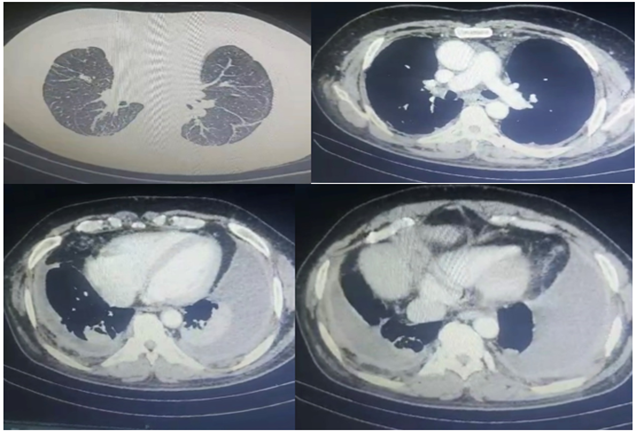

A 69-year-old male came to our emergency with complaints of breathlessness for 3 months which was insidious onset and progressive. He had chest tightness, and cough with whitish mucoid sputum for 1 month. He initially had chest pain 3 months back but it decreased gradually. There was no history of fever, He had a history of pulmonary tuberculosis 40 years back for which he took 9 months of antitubercular therapy. He was a smoker but did not consume alcohol. He was hypertensive for 10 years and was nondiabetic. There was no history of trauma, surgery, or any other interventions in the past. On admission, his blood pressure was 134/90 mm Hg, pulse 102/min, oxygen saturation 88% on room air, and respiratory rate 32/min. There was no pallor, icterus, cyanosis, clubbing, pedal edema, or lymphadenopathy. On inspection, there were decreased chest movements in infra-axillary and mammary areas. On percussion stony dull sound was noticed in the infrascapular, and infra-axillay regions bilaterally. On auscultation, there were decreased air entry in the infrascapular regions bilaterally and S3 gallop prominent Electrocardiogram (ECG) was suggestive of right bundle branch block pattern. Trop T was negative. Chest radio-graph showed blunting of bilateral costophrenic angles. Blood investigations were as follows: hemoglobin 13.2 gm/dl, leucocytes 8110/mm3, platelets 4.24 lakh/mm3, blood urea 31.4 mg/dl, creatinine 0.91 mg/dl, bilirubin 0.5 mg/dl, AST 43 IU/L, ALT 56 IU/L, total protein 5.6 gm/dl4, LDL 98 mg/dl, HDL 29 mg/dl, Triglyceride 125 mg/dl, VLDL 25 mg/dl, blood glucose 138 mg/dl. The urine examination was within normal limits. The patient's abdominal ultrasound was normal. Patients' viral markers HIV, HBsAg, and HCV was negative. Sputum Ziehl neelsen stain and gene xpert were negative for tuberculosis. Thoracic ultrasound revealed bilateral pleural effusion. Under ultrasound guidance, thoracocentesis was done. Pleural fluid was milky in color and its biochemical pathological and microbiological reports were as follows pleural fluid protein 4.06 gm/dl, glucose 137mg/dl, ADA 12.6 IU/L, LDH 806 mg/dl, triglyceride 381 mg/dl, cholesterol 51 mg/dl, gene xpert of pleural fluid was negative for mycobacterium tuberculosis. The culture was sterile. The total leucocyte count was 1000 of which 95%were lymphocytes and 5% neutrophils cytology was negative for malignant cells and no fungal element was seen. Thus, a diagnosis of chylothorax was made. Contrast-enhanced computer tomography was suggestive of a patchy area of consolidation/collapse with few specs of calcifications within and adjacent thin atelectatic bands seen in basal segments of bilateral lower lobes. There was no mediastinal lymphadenopathy. Bilateral pleural effusion seen with underlying atelectatic changes. 2D Electrocardiography revealed dilated cardiac chambers, severe left ventricles dysfunction with ejection fraction of 25-30%. Thus, after ruling out other possible causes of chylothorax, we made a diagnosis of chylothorax due to congestive heart failure which is a rare entity. After starting the treatment for congestive heart failure, patient showed significant improvement symptomatically and Chest radiograph also showed decreased amount of pleural effusion. He was discharged on stable vitals with oxygen saturation 95% on room air.

Figure 3: Contrast Enhanced Computer Tomography of chest.